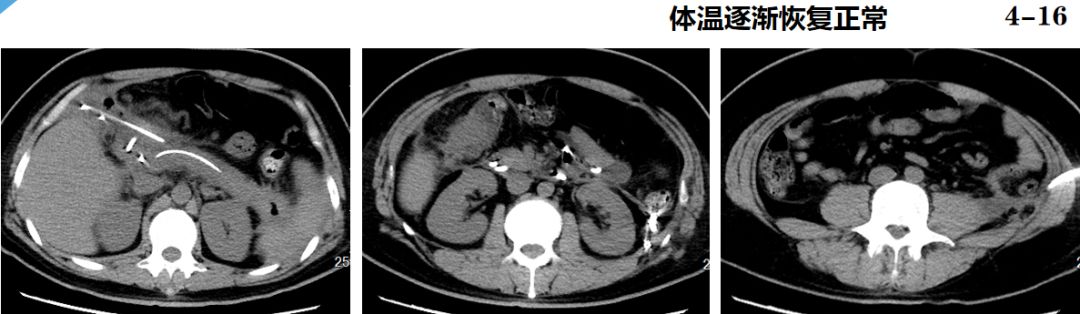

临床转归

4.20 拔除引流管

4.23 康复出院

10.9 随访,正常生活